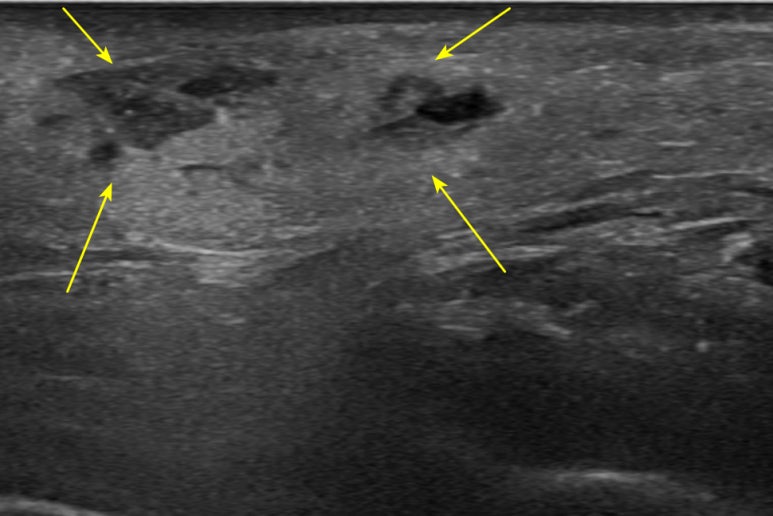

이렇게 큰 혈종**은 없어지는데 더 오랜 시간이 걸립니다. 초음파 가이드 하에 혈종을 빼내기로 합니다. 초음파 유도하 혈종 흡인 니들의 정확한 위치를 파악하고 주사기로 뽑아내는데요. 실시간으로 크기가 줄어드는 것이 보이시나요?

어혈 치료 전 후 혈종을 제거한 직후의 모습니다. 까만 영역의 혈종이 대부분 사라졌습니다. ## 육안으로도손으로 눌러서도딱딱한 혹이 바로 없어져환자분은 만족해하셨고, 나머지 멍도 빨리 빠질 수 있도록 침 치료를 시행하였습니다. * * * ## 어혈이란?*혈류순환 정체(뭉친 피)**와